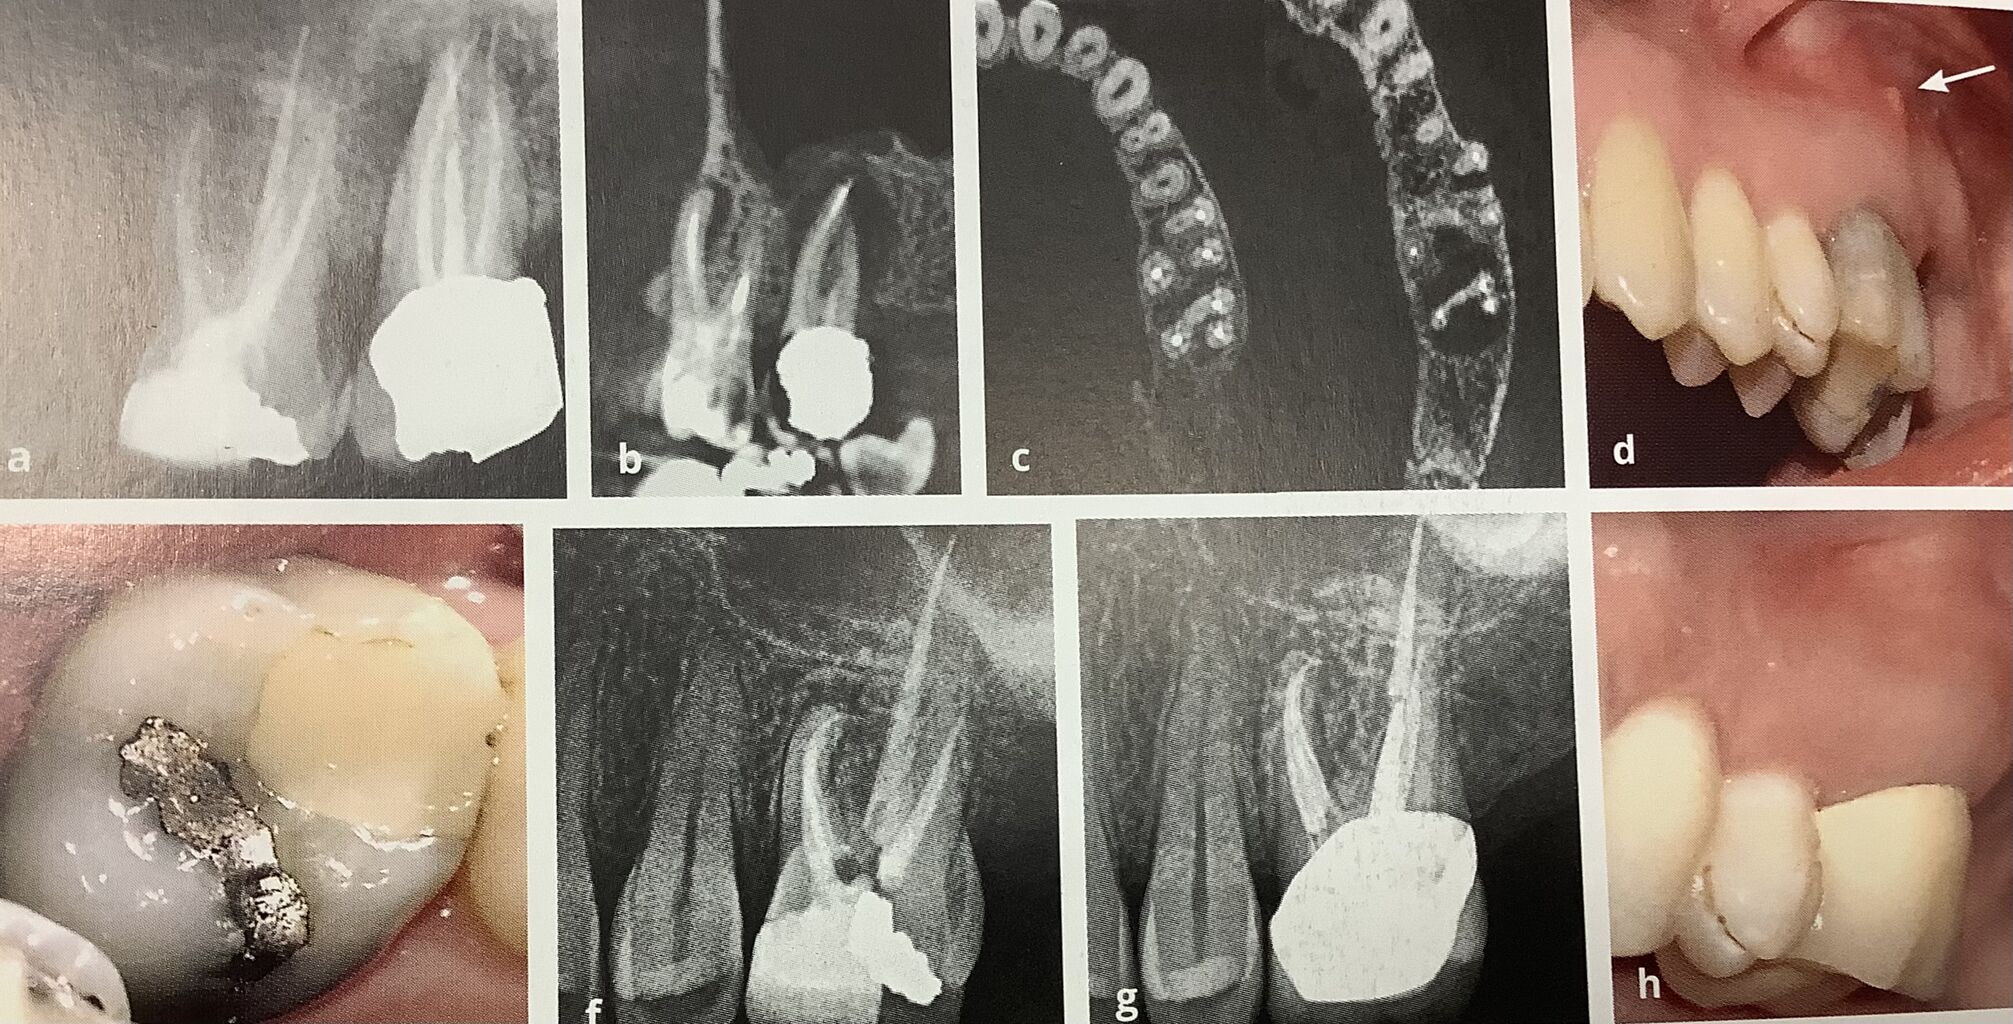

上から治療の経過ですね。

左上の奥歯の感染症状が続いていたそうです。

左の6、7ともに根管治療をされていますが、根っこの先にカゲがあります。

真ん中のCTで横から見た画像ですと、7番の病気の方が大きいようです。

上から見た断面では、両方とも4番目の神経の治療がされていないようです。

患者さんは7が犯人と思ったので、抜くことを希望されたそうです。

が、左上の写真のように3週間後に瘻孔、膿が出てきました。

で、6番の再根管治療を希望されて、見逃していた神経を含めてキレイにされました。

下が治療後で6ヶ月後で、すっかり治ったそうです。